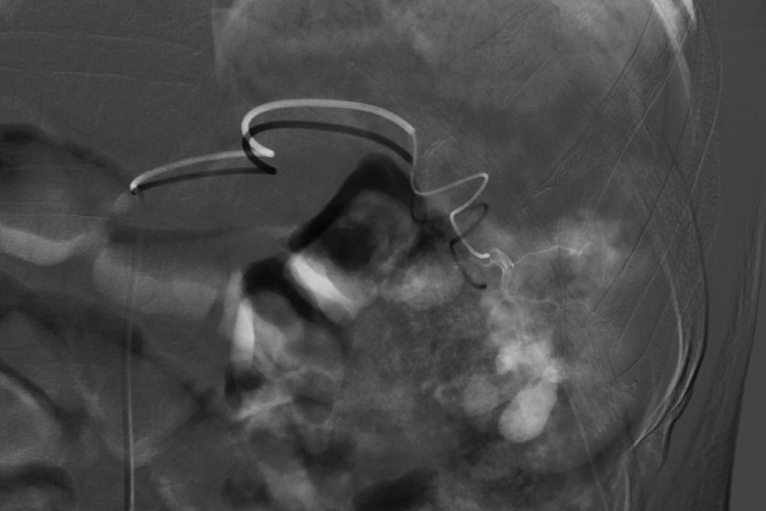

患者龚先生,58岁,因车祸导致胸腹联合伤入院,确诊为肋骨骨折、脾脏挫伤,并伴有肾病综合征等基础疾病。在治疗监测过程中,医生发现其早期脾损伤后继发脾内动脉瘤,进一步增加了治疗难度。据心胸血管甲乳外科副主任贺锋介绍,传统治疗通常需切除脾脏以确保安全,但脾脏作为重要免疫器官,切除后将不可再生。且开腹手术创伤大、恢复慢,对合并基础疾病患者风险较高。经多学科详细病例讨论,团队决定采用更为精准的脾动脉栓塞术。在数字减影血管造影设备引导下,医疗团队凭借娴熟技术,精准定位并栓塞脾脏出血动脉,成功阻断病灶血供。术后患者恢复顺利,短时间内即可下床活动,各项指标逐步恢复正常,实现了“创伤小、费用低、康复快”的治疗效果。